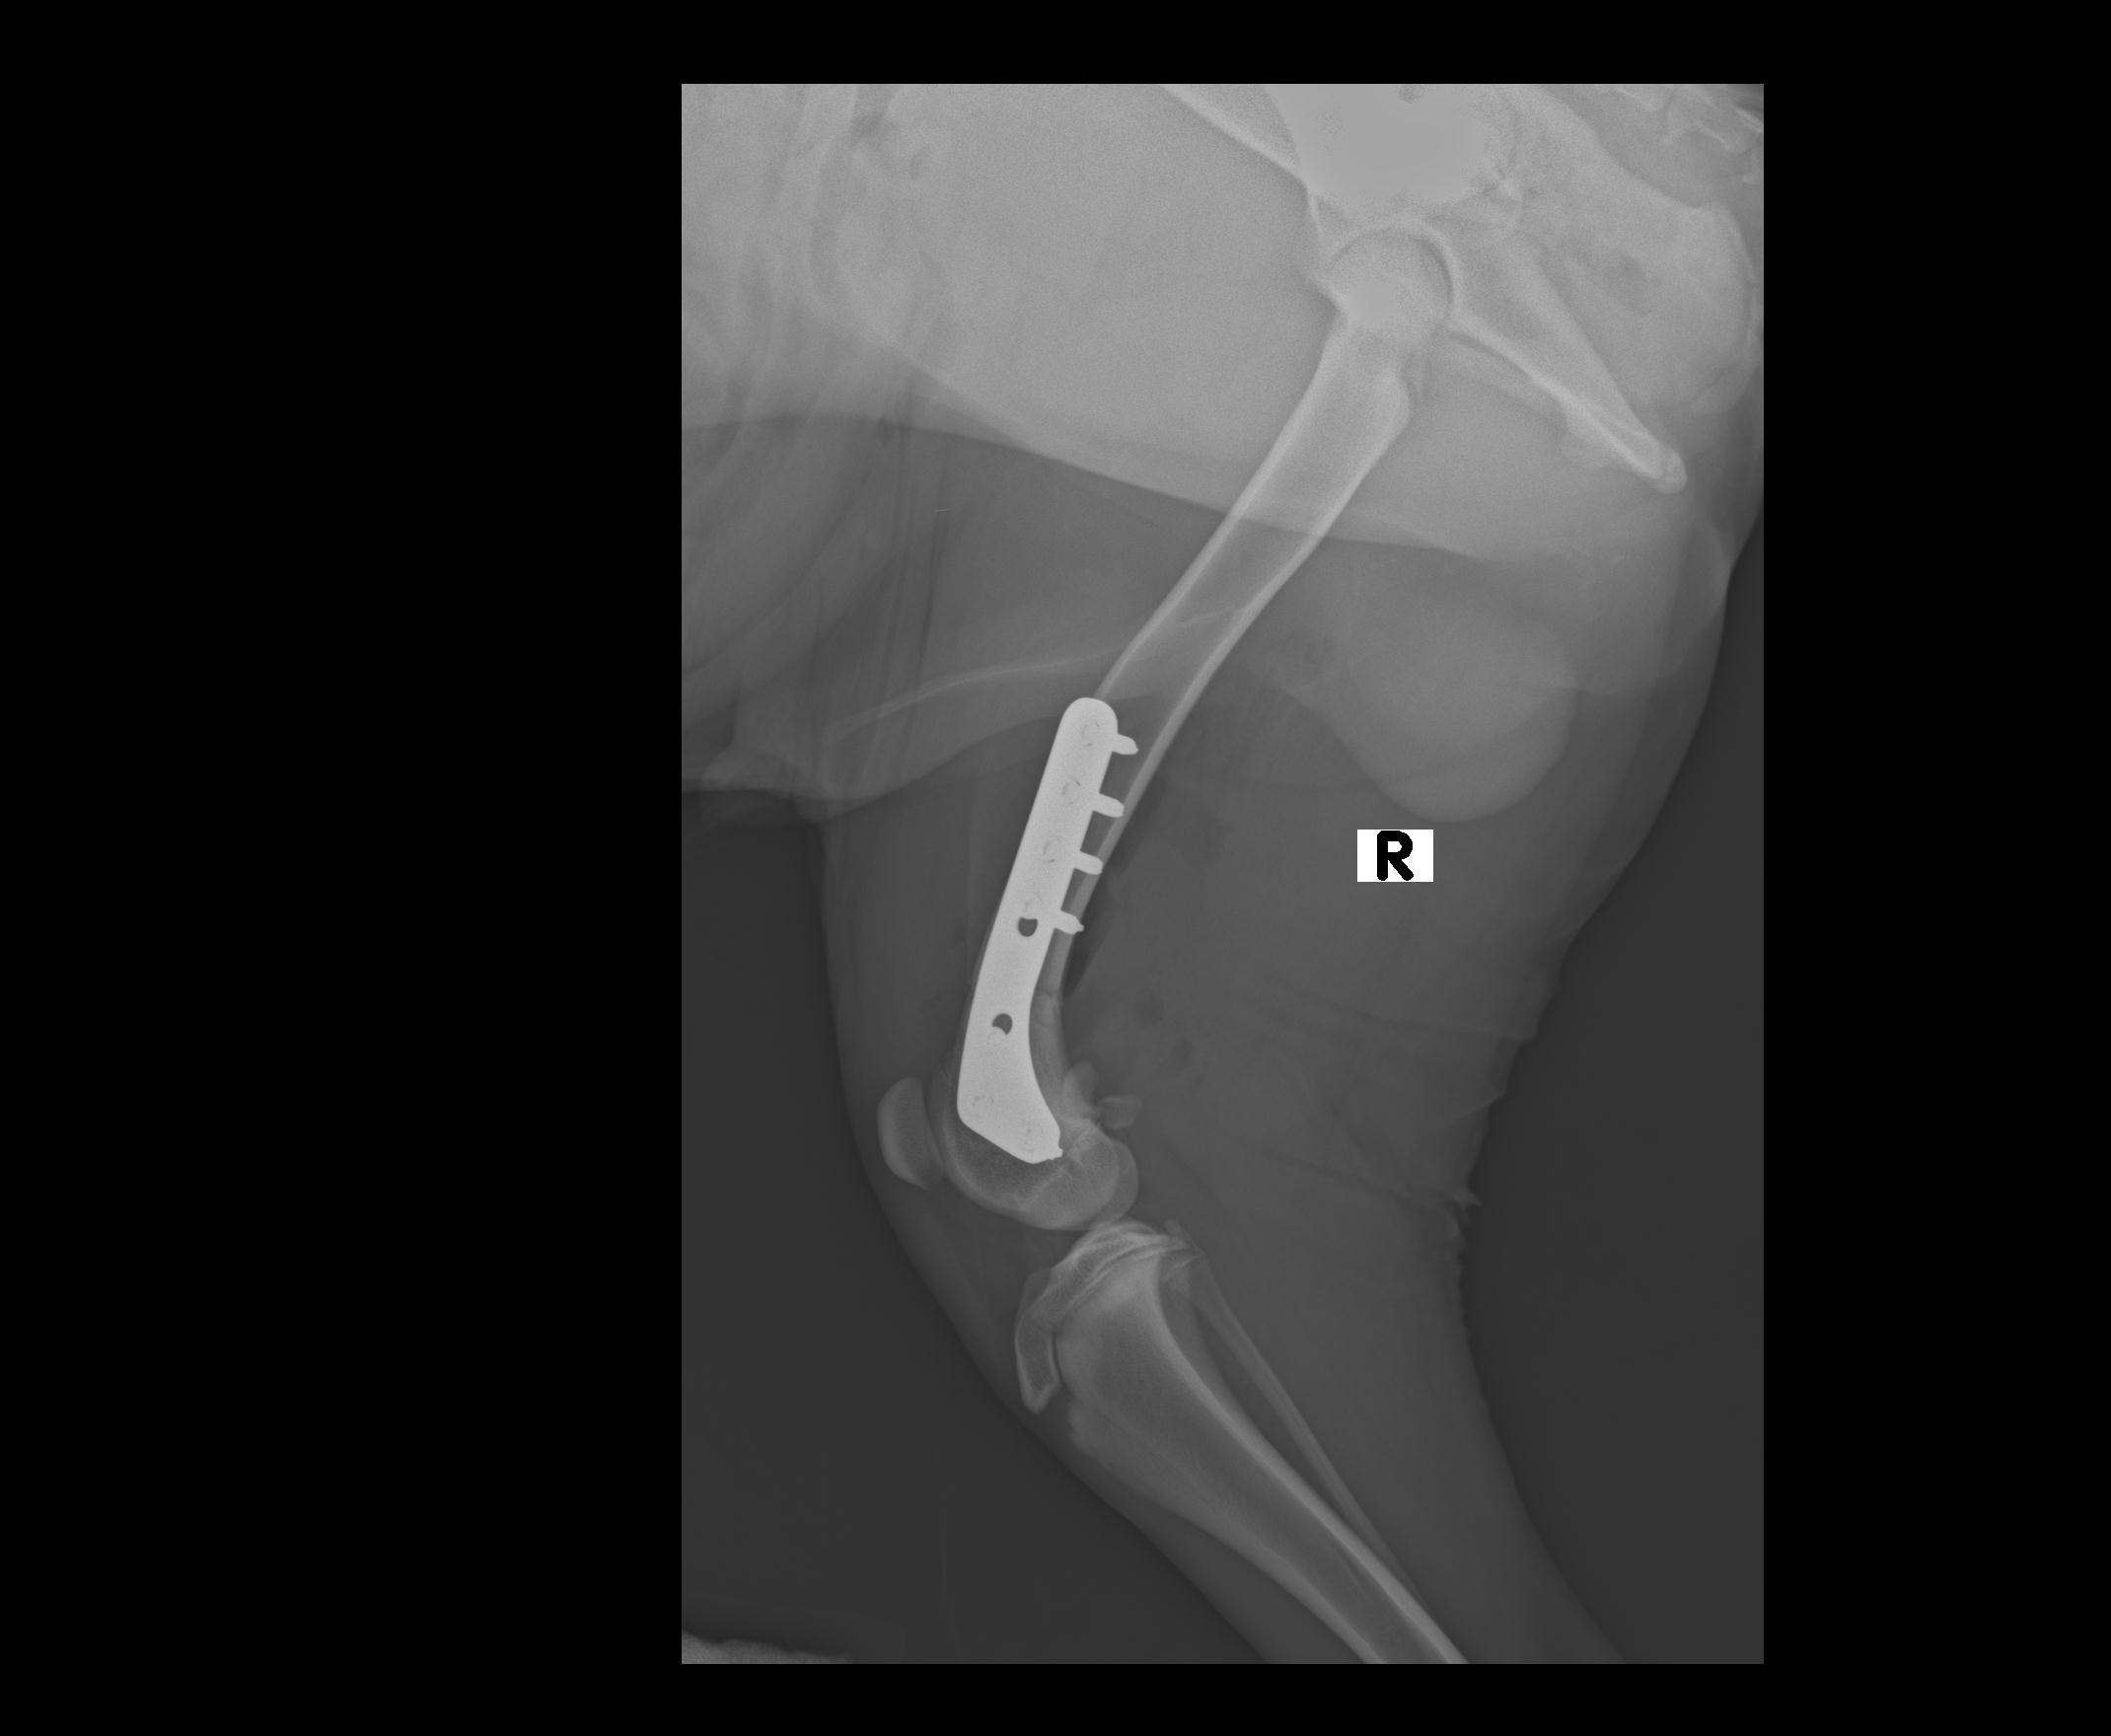

ROBY0002